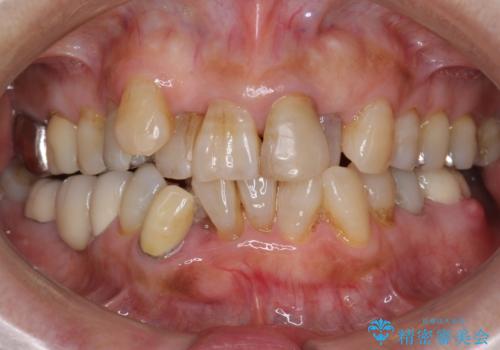

親知らずの移植 4年半経過症例 70代女性

- 親知らずの移植治療から4年半経過した患者様です。

他の歯の治療をご希望され、数年ぶりに来院して下さいました。

4年半前に行った自家歯牙移植に大変ご満足頂き、ご家族も紹介して下さいました。

自家歯牙移植は40歳以上の場合、若年者に比べ成功率が低くなるとの報告もありますが、状態によっては移植が可能な場合もあります。